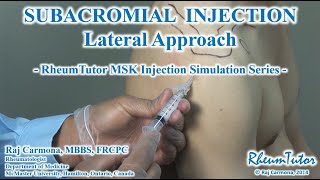

Ultrasound guided subacromial injection (PRP) Subacromial Injection - Lateral Approach

Subacromial Injection - Lateral Approach How to do a Subacromial Shoulder Injection

Ultrasound guided subacromial injection (PRP) Subacromial Injection - Lateral Approach

Subacromial Injection - Lateral Approach How to do a Subacromial Shoulder Injection